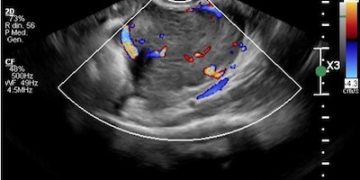

Casi del Mese di Dicembre 2024

Cari soci, finalmente on line le soluzioni dei casi del mese di Dicembre. Grazie a Sara Zullino e Mara Albanese!! Caso 1 - video [pdf-embedder url="https://www.sieog.it/wp-content/uploads/2024/12/Casodelmese_Dicembre2024caso-risposte_gineco.pdf"...